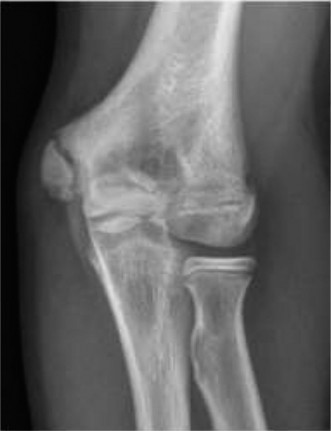

Standard orthogonal radiographs of the ankle, including anteroposterior, lateral, and mortise views, are the initial diagnostic modality. However, the complex, multi-planar nature of transitional fractures makes plain radiography insufficient for definitive preoperative planning. Plain films frequently underestimate the degree of articular displacement and the number of fracture fragments.

A high-resolution Computed Tomography scan with sagittal, coronal, and three-dimensional reconstructions is mandatory for all suspected triplane and Tillaux fractures. The CT scan allows the orthopedic surgeon to precisely map the fracture lines, quantify the articular step-off, identify the presence of intercalary articular fragments, and plan the exact trajectory for internal fixation. In a triplane fracture, the CT scan will clearly delineate the coronal metaphyseal fragment, the sagittal epiphyseal fragment, and the axial physeal separation. Identifying the exact location of the Chaput fragment and the integrity of the syndesmosis is critical for determining the surgical approach and the necessity of syndesmotic stabilization.